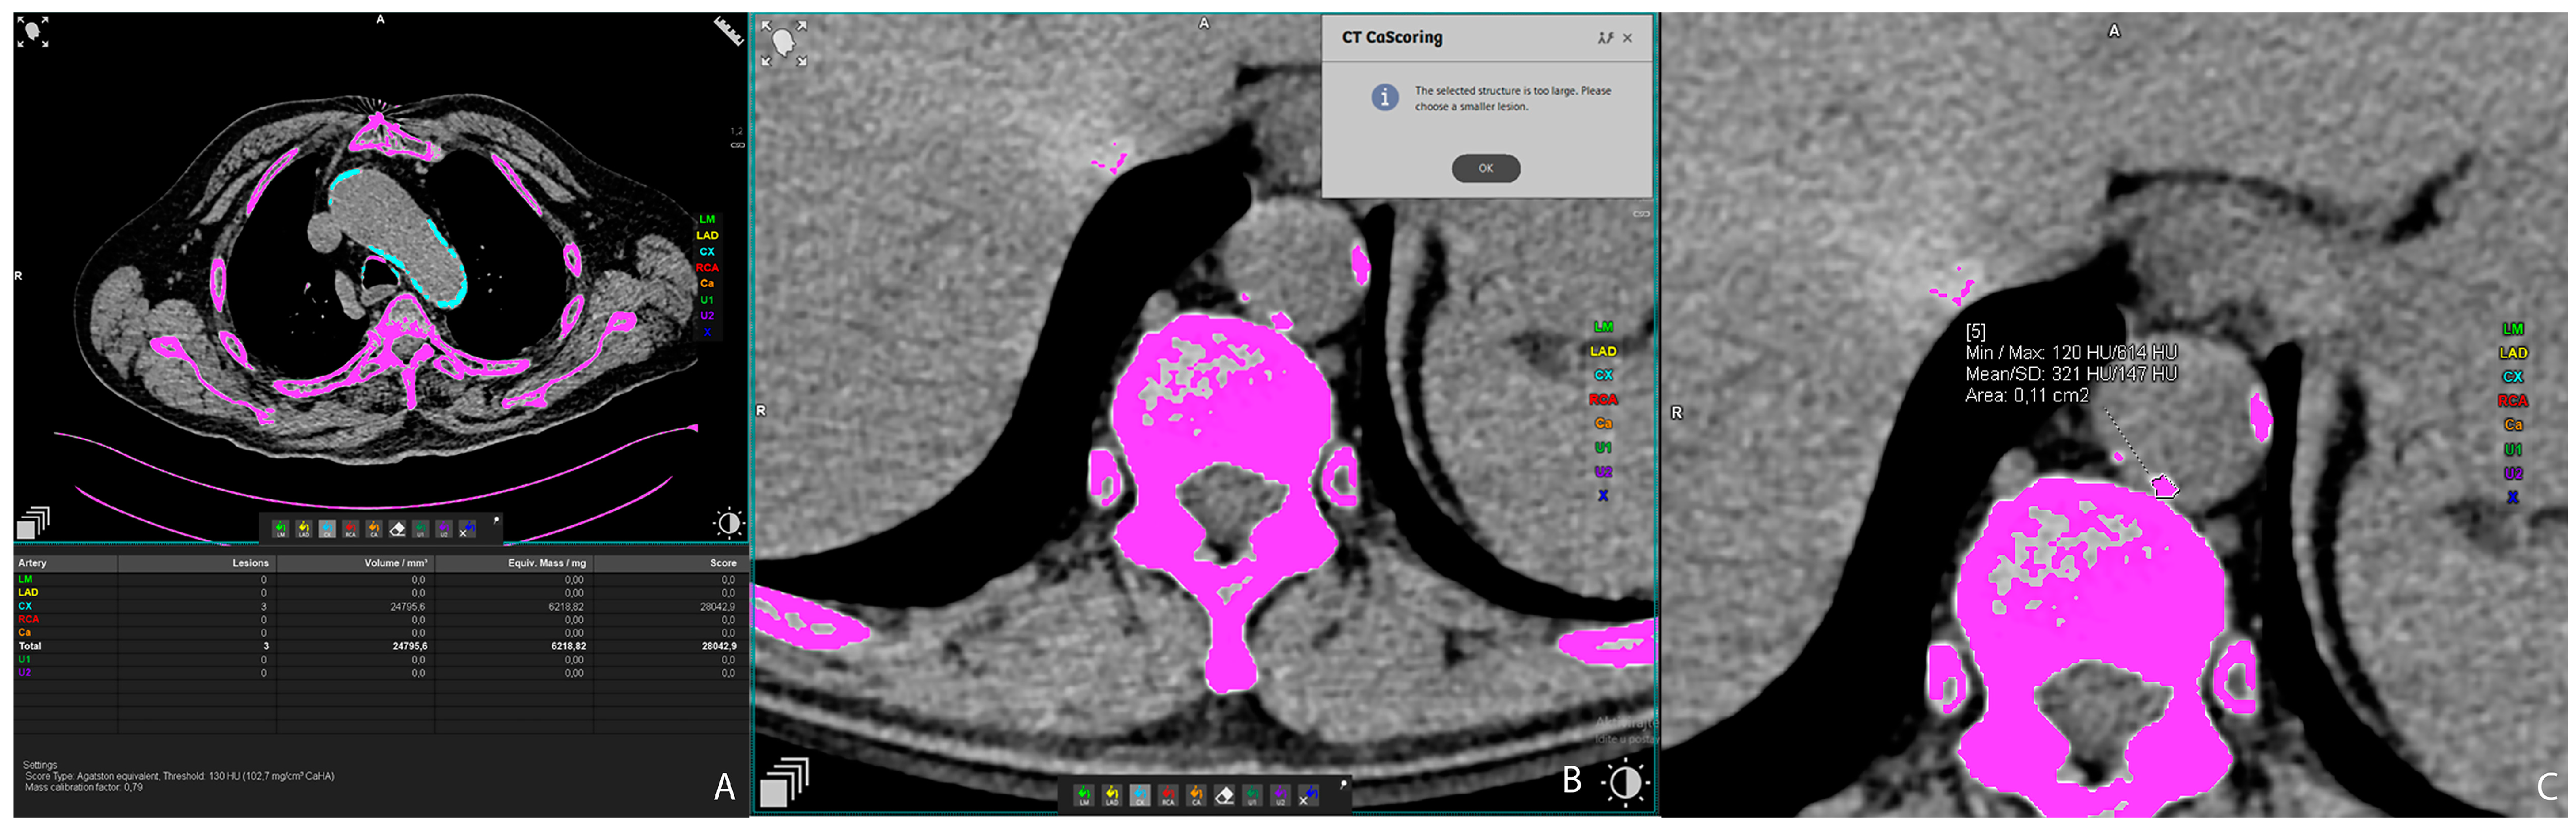

2.2. Vascular Calcification Measurement